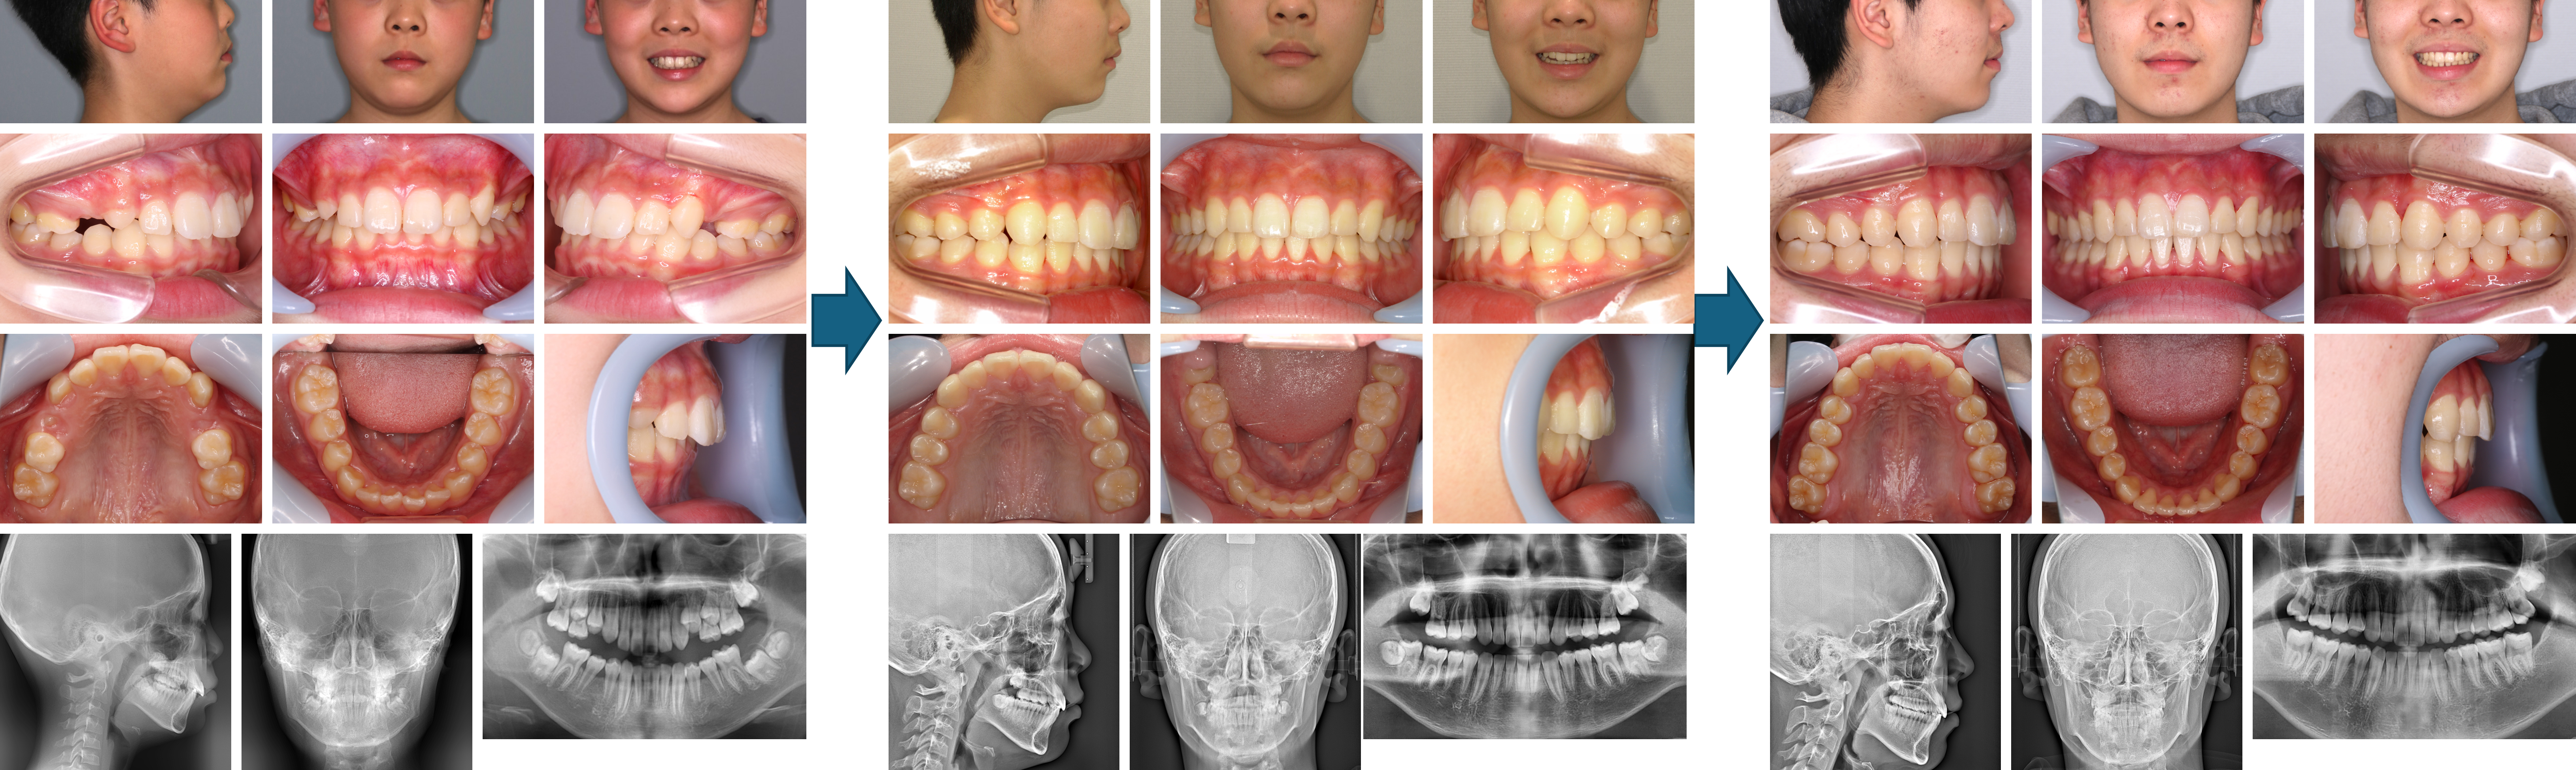

【治療例 K7031】初診時年齢:7歳0か月 / 性別:男性 / 主訴:下の乳歯が抜けて生えてきた永久歯の歯並びが悪い

治療の概要:初診時年齢7歳1か月の男児で、下顎前歯1歯の萌出状態を主訴に来院した。定期的に口腔内写真およびエックス線写真を撮影し、永久歯への交換を含めた経過観察を行った。その間、必要に応じて乳歯の削合や抜歯を行い、乳歯から永久歯への円滑な交換を図った。永久歯萌出後も経過観察を継続し、中学校受験終了後の13歳5か月よりアライナー型矯正装置(インビザライン®)による治療を開始した。その結果、小臼歯抜歯やIPRを行うことなく、上下前歯部の過蓋咬合ならびに叢生は改善し、適正なオーバーバイトおよびオーバージェットを獲得した。

主訴:下の乳歯が抜けて生えてきた永久歯の歯並びが悪い

診断名:下顎前突を伴う叢生症例

使用した主な装置:アライナー型(マウスピース型)矯正装置(インビザライン®)

抜歯/非抜歯および抜歯部位:非抜歯

治療期間:7年2か月

治療回数:34回

アライナー枚数:初回22枚